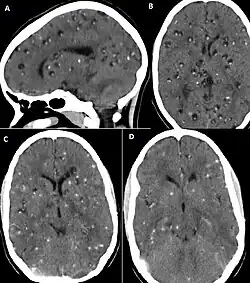

CT scan of neurocysticercosis before and after treatment

Brain CT of neurocysticercosis before (A and B) and after (C and D) treatment with albendazole[54]

Neurocysticercosis is a persistent infection and symptoms appear months or years later. As a result, removing the parasite is not an emergency, and the first step in treating those with neurocysticercosis is often aimed at minimizing the symptoms. This may be done with the use of antiepileptic, antiedema, analgesic, or anti-inflammatory drugs.[55] Carbamazepine is commonly used to control seizures.[47][56] Antiepileptic medications may be used till after a year without seizures.[57] Surgery, acetazolamide, steroids, or mannitol may be used to help manage intracranial hypertension.[55][58]

The two most commonly used antiparasitic medications are albendazole, an imidazole that inhibits glucose absorption and metabolism in the parasite, and praziquantel,[61] an isoquinoline which triggers parasite paralysis by altering calcium pathways and homeostasis.[52] Taking days to months to work,[62][47] antiparasitic drugs are only appropriate for the treatment of vesicular viable cysts or cysts in the early colloidal phases of development, and are ineffective against calcified cysts.[52][63] Antiparasitic drugs cannot be given when there is a preexisting risk of developing hydrocephalus, such as with sub-arachnoid neurocysticercosis or encephalitic neurocysticercosis; in these cases, the inflammation that occurs after treatment may pose a significant risk of rapidly raising intracranial pressure and death.[64]